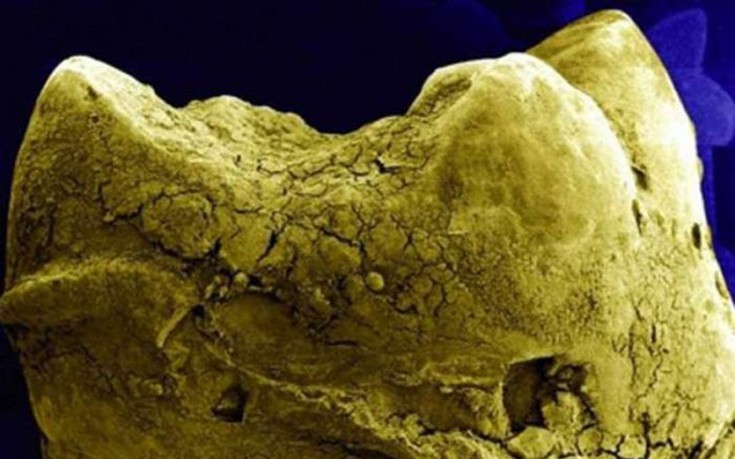

Στο μικροσκόπιο μπορεί να δει κανείς τον κόσμο με μια εντελώς διαφορετική ματιά. Έτσι και το σώμα μας κρύβει λεπτομέρειες και όταν το δει κανείς κάτω από το μικροσκόπιο, δεν μπορεί πάντα να αναγνωρίσει τι βλέπει.

Δείτε παρακάτω μερικά παραδείγματα από όργανα του σώματος ή για παράδειγμα πώς είναι η οδοντική πλάκα…